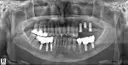

상담원분이 친절하시고 너무 좋았어요! 임플란트 어디서 해야하나 많이 고민했는데 가격도 저렴하니 좋더라구요~ 엘베가 느린건지 타는 사람인지 많은건지 모르겠지만 병원 들어갈때 오래 걸리는 느낌이라 더 긴장되고ㅜㅜ 임플란트가 처음이라 너무 걱정됐는데 괜한 걱정했네요🤭 원장님이랑 간호사분들 너무 친절하셨어요! 과잉진료 이런것도 전혀 없으시구 꼼꼼하니 잘된것 같아서 만족합니다❤️🔥